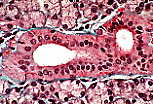

被覆上皮